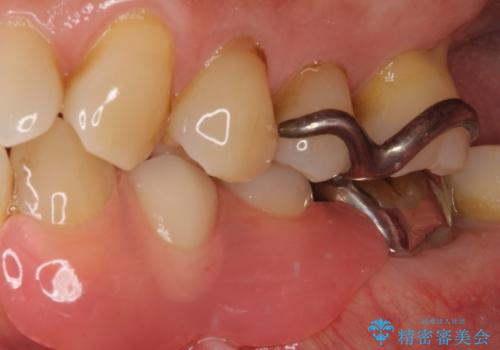

- 近医にて抜歯が必要と言われたとのことで来院された患者様です。

顕微鏡下で確認したところ、歯根に及ぶ破折線が認められたため、抜歯を行うこととしました。

インプラント治療をお勧めしましたが、取り扱いや手入れが煩雑でも良いとのことで、可撤性義歯(入れ歯)にて補綴治療を行うこととしました。